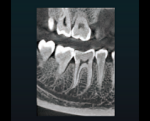

口腔内を高画質で再現することができるため、より正確な診断が可能です。

歯の根の形態や先端の方向など、細部の把握が可能です。